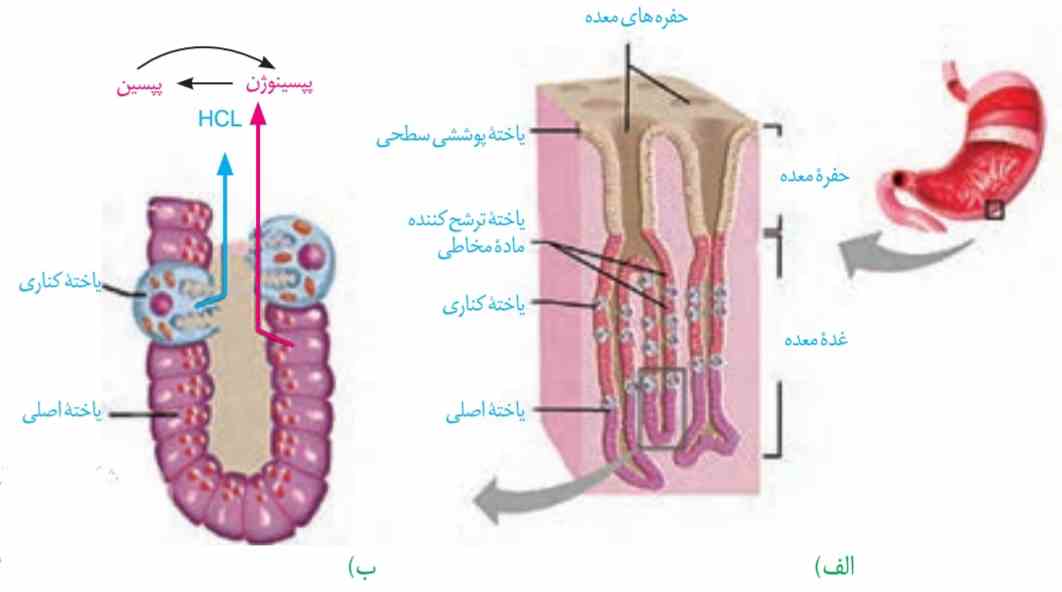

شیرهٔ معده: یاختههای پوششی مخاط معده در بافت پیوندی زیرین فرو رفتهاند و حفرههای معده را بهوجود میآورند. مجاری غدههای معده، به این حفرهها راه دارند. یاختههای پوششی سطحی مخاط معده و برخی از یاختههای غدههای آن، ماده مخاطی فراوان ترشح میکنند که به شکل لایهٔ ژلهای چسبناکی، مخاط معده را میپوشاند. یاختههای پوششی سطحی، بیکربنات (–HCO۳) نیز ترشح میکنند که لایهٔ ژلهای حفاظتی را قلیایی میکند (شکل ۹). به این ترتیب سد حفاظتی محکمی در مقابل اسید و آنزیم بهوجود میآید.

شکل ۹ـ الف) غدههای معده ب) یاختههای غدههای معده، مواد مختلف شیرۀ معده را ترشح میکنند.

یاختههای اصلی غدهها، آنزیمهای معده را ترشح میکنند. پیشساز پروتئازهای معده را بهطور کلی پپسینوژن مینامند. پپسینوژن بر اثر کلریدریک اسید به پپسین تبدیل میشود. پپسین خود با اثر بر پپسینوژن، تولید پپسین را بیشتر میکند (شکل ۹). آنزیم پپسین، پروتئینها را به مولکولهای کوچکتر تجزیه میکند. یاختههای کناری غدههای معده، کلریدریک اسید و عامل (فاکتور) داخلی معده ترشح میکنند. عامل داخلی معده، برای ورود ویتامین B۱۲ به یاختههای رودهٔ باریک ضروری است. اگر این یاختهها تخریب شوند یا معده برداشته شود، علاوه بر ساخته نشدن کلریدریک اسید، فرد به کمخونی خطرناکی دچار میشود؛ زیرا ویتامین B۱۲ که برای ساختن گویچههای قرمز در مغز استخوان لازم است، جذب نمیشود و زندگی فرد به خطر میافتد.